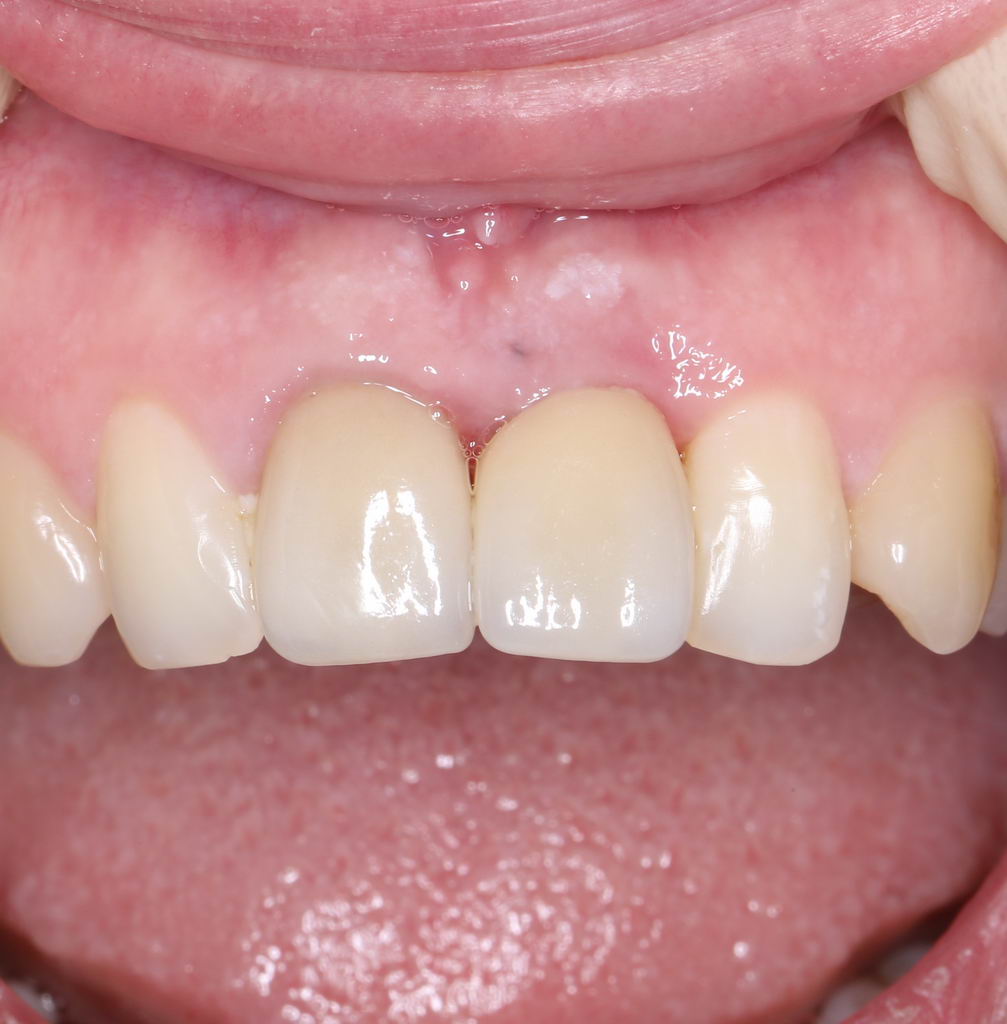

Установка формирователя десны, стандартного или индивидуального — это «классическое» завершение операции немедленной имплантации, поскольку, при условии хорошей стабильности имплантата и отсутствии проблем со слизистой оболочкой, разумно проводить формирование десневого контура одновременно с интеграцией имплантата. Фактически, это даёт возможность объединить все хирургические этапы в одну операцию, через несколько месяцев установить на имплантат коронку (для этого даже не требуется анестезия) и завершить лечение с минимальной травмой и максимальным результатом.

Но это еще не всё. Не каждый пациент готов оставаться без зуба на период проведения имплантологического лечения. Поэтому в некоторых случаях мы можем зафиксировать на только что установленный имплантат временную коронку, замок или даже целый временный протез:

Таким образом, мы добиваемся улучшения качества жизни наших пациентов в кратчайшие сроки. Не говоря уже о том, что сокращение этапов стоматологического лечения приводит к уменьшению его стоимости.